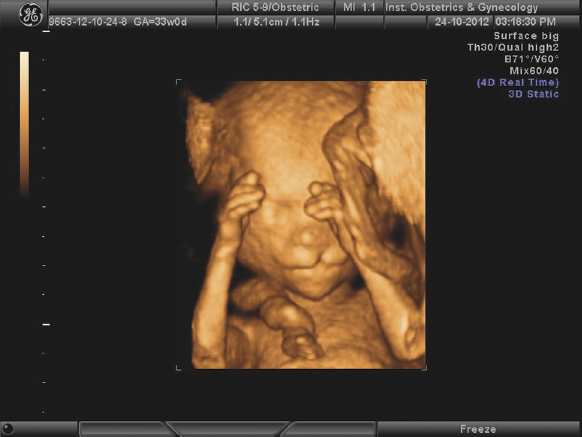

Большинство особенностей развития, установленных пренатально, были подтверждены после рождения. Многие дети (более 60 %) успешно прооперированы после рождения и наблюдаются у профильных специалистов. Нам известны исходы оперативного лечения и наблюдения новорожденных с выявленными внутриутробно spina bifida occulta, гастрошизисом, омфалоцеле, атрезией ануса, атрезией пищевода, некоторыми сложными пороками сердца (рис. 3, 4). Все пациентки с выявленными пороками развития у их плодов были направлены к генетикам, некоторым из них было выполнено пренатальное кариотипирование. В случае неблагоприятного прогноза после заключения пренатального консилиума некоторые беременности были прерваны по желанию пациенток.

Рис. 3. Омфалоцеле плода, 20 недель беременности